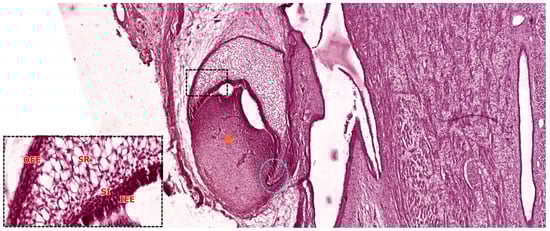

3.3.2. Late Bell Stage

Differentiation of Odontoblasts

Differentiation of Ameloblasts